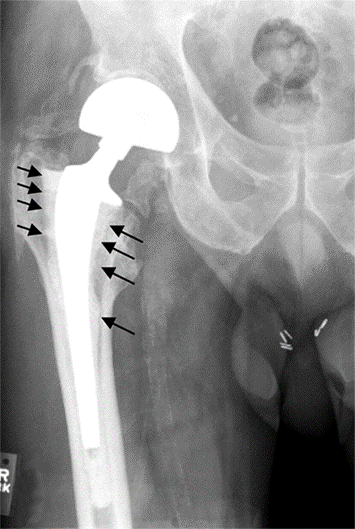

Il più delle volte l'usura della protesi non causa grossi problemi. Potresti notare un leggero dolore, percepire dei crepitii o degli scricchiolii o

sviluppare una lieve zoppia. Tuttavia, spesso l'unico modo per evidenziarla precocemente sono le radiografie. Se evidenziata precocemente, l'intervento

chirurgico di revisione consisterà solamente nel cambiare la superficie in plastica usurata e quindi il recupero funzionale sarà più facile rispetto ad

una chirurgia di revisione completa.

Quando il dolore e la sensazione di scatto articolare a livello dell'articolazione sono più frequenti, spesso è già troppo tardi per sostituire soltanto la

componente usurata.

In questi casi l'intervento di revisione consisterà nella sostituzione anche delle componenti metalliche. È un po' come se ignorassi il fischio che proviene

dai freni quando freni nella tua macchina, quando poi la porti dal meccanico questo scopre che il danno si è esteso, adesso anziché cambiare solo le pastiglie,

deve essere sostituito l'intero sistema frenante.